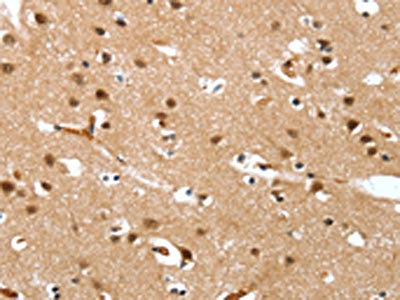

The image on the left is immunohistochemistry of paraffin-embedded Human thyroid cancer tissue using CSB-PA968280(DEFA4 Antibody) at dilution 1/20, on the right is treated with synthetic peptide. (Original magnification: ×200)

The image on the left is immunohistochemistry of paraffin-embedded Human brain tissue using CSB-PA968280(DEFA4 Antibody) at dilution 1/20, on the right is treated with synthetic peptide. (Original magnification: ×200)